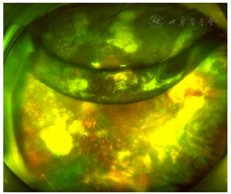

裂隙灯检查:双眼眼前节及右眼眼底检查未见明显异常,左眼眼部检查见大量黄白色渗出及点片状出血,颞侧可见视网膜下增殖膜,鼻下方见局部视网膜球形隆起(图1)。